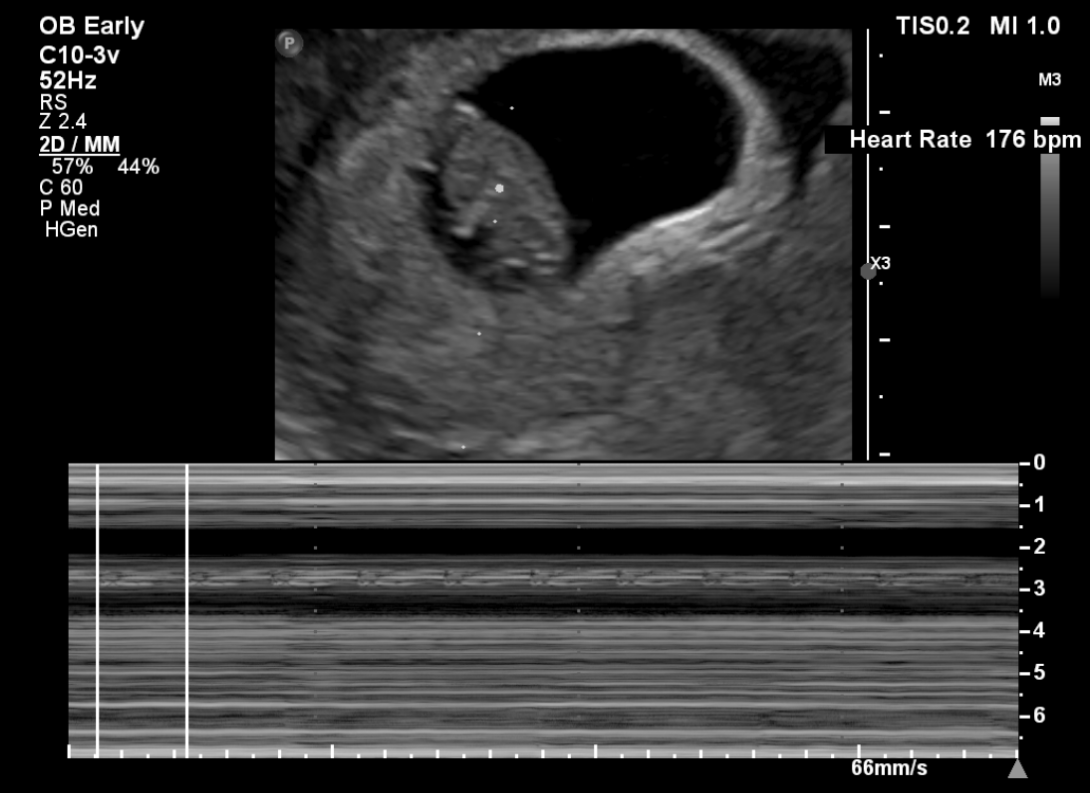

임신 8주 차 초음파 검사 ( 8주 5일 차 초음파 사진)

첫 트롱이 사진 짜잔~~ 젤리곰 이다 >. < 주수에 맞게 잘 자라고 있는 트롱이~ 심박수도 176 bpm으로 정상!

사실 초음파 검사 당시엔 아기 모습을 보지 못했어요~ 검사해주는 분께서 화면으로 보여주지도 않고 아무 말 없이 혼자 보면서 검사를 하시더라고요~ 그래서 저희 남편만 화면으로 확인하면서 너무 귀엽다고 잘 자라고 있다고 ㅠㅠ 저를 안심시켜줬습니다.

검사가 끝나고 전 메일로 받은 초음파 사진으로 처음 우리 아이를 봤어요~! 보고 나서 너무 귀엽고 제 뱃속에 이 작은 생명이 있다는 게 너무 신기해서 울었어요~ ㅜ.ㅜ~ ㅋㅋㅋ